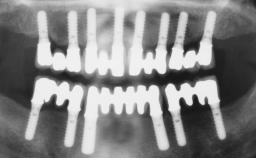

Immediate Loading of Four Implants in the Mandible and Six Implants in the Maxilla and Final Restoration with a Full-Arch Metal Framework FDP and a Full-Arch CAD/CAM Zirconia Framework FDP

# of Implants 10

Type of Implants Two-Piece